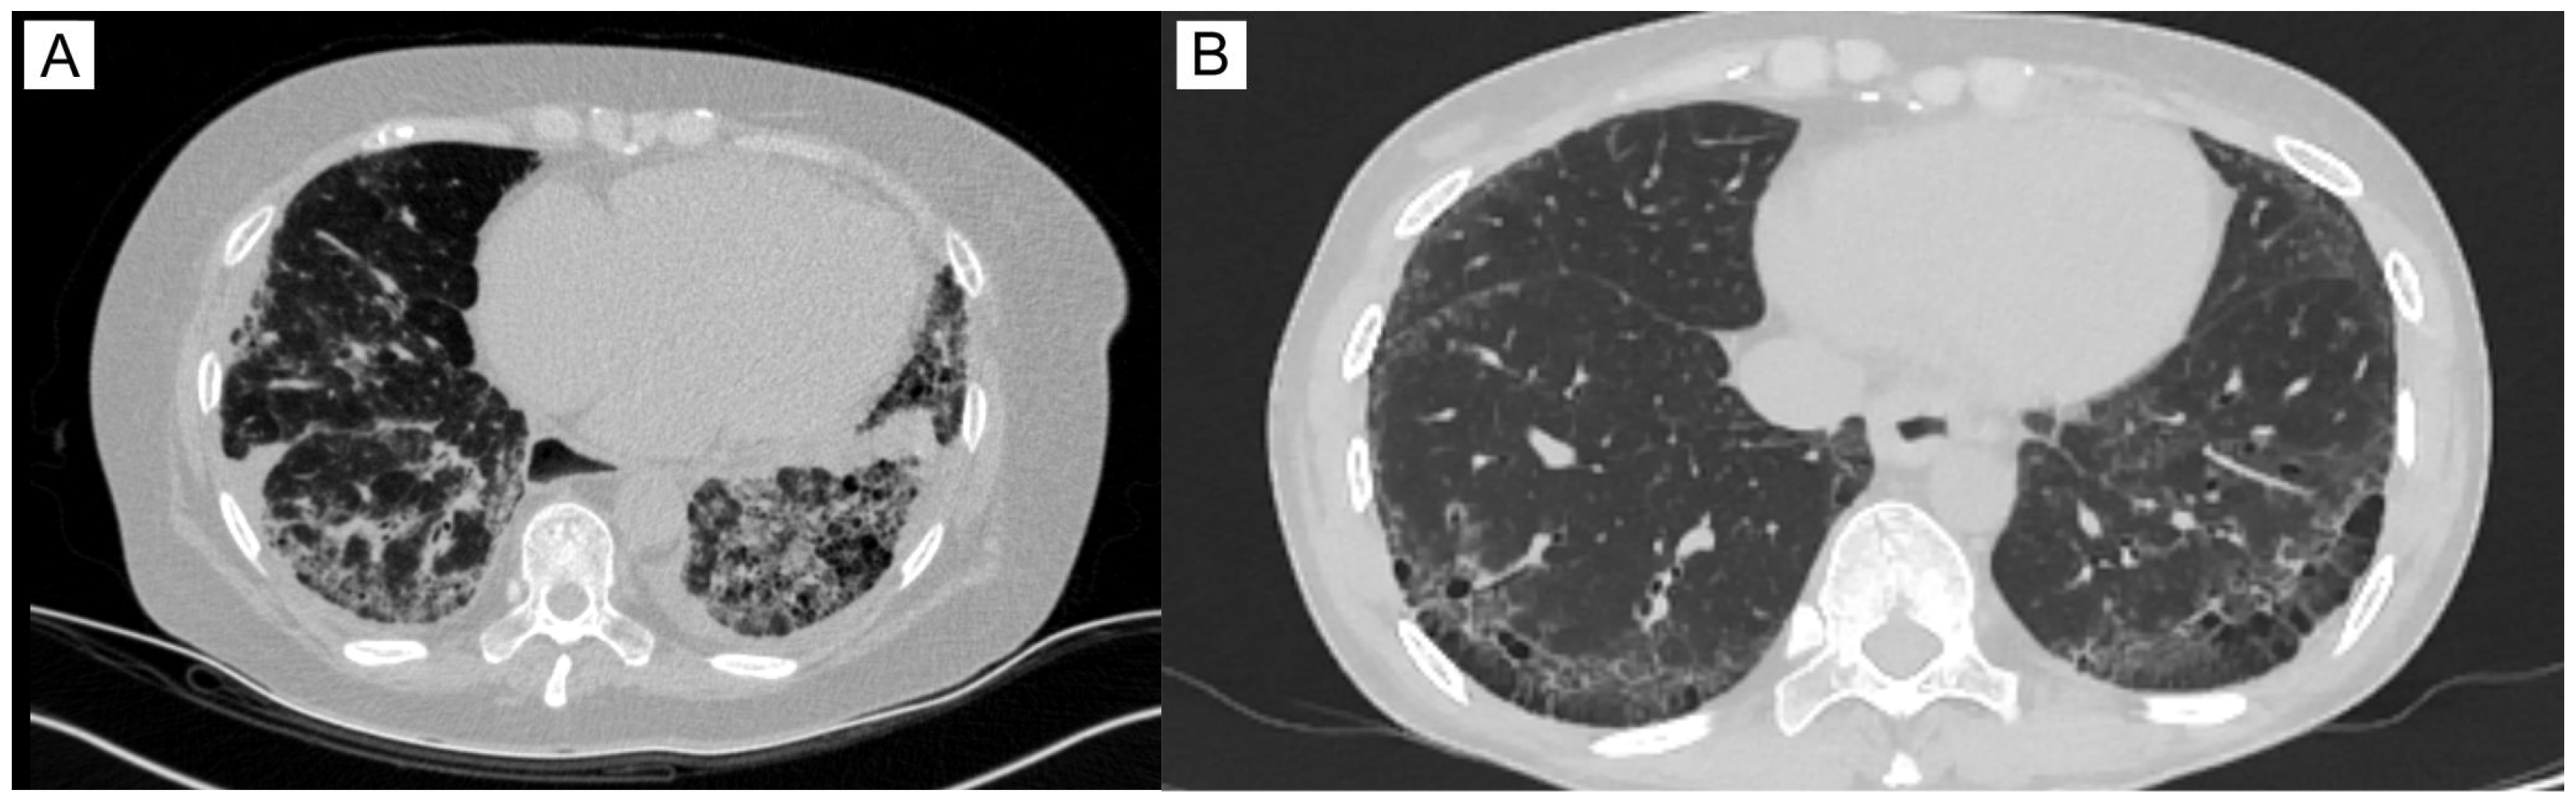

The main group consists of 26 Kazakh patients who have had SSc for the last 9.65 ± 9.8 (mean ± SD) years. mRSS was equal to 16 ± 7.2 and EScSG to 3.54 ± 2.18. In the majority of patients, 96% (25/26), various skin lesions were observed, including skin thickening, varying in extent, dense edema, “purse-string” mouth, sclerodactyly, digital ulcers, puffy fingers, and hyper- and hypopigmentation (Figure 1). Articular injury manifested in the form of polyarthralgia or arthritis was found in 23/26 patients (88%), as well as vascular disturbances (Raynaud’s phenomenon). Overall, 19 of 26 patients had frequent lesions of the gastrointestinal tract, in the form of esophagitis (73%). Seventeen patients suffered from lung impairment, which manifests as interstitial lung disease (SSc-ILD) with signs of non-specific interstitial pneumonia (NSIP, more common) or usual interstitial pneumonia (UIP) that has been found on high-resolution computed tomography (Figure 2). Ten patients (38%) were diagnosed with a secondary Sjögren’s syndrome, characterized by xerostomia and xerophthalmia. Three patients had thyroid impairment (12%) and two cardiovascular disorders (7.6%, Supplementary Table S1).